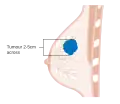

After the tumor is evaluated, the breast cancer case is staged using the American Joint Committee on Cancer and Union for International Cancer Control's TNM staging system.[54] Scores are assigned based on characteristics of the tumor (T), lymph nodes (N), and any metastases (M).[55] T scores are determine by the size and extent of the tumor. Tumors less than 2 centimeters (cm) across are designated T1. Tumors 2–5 cm across are T2. A tumor greater than 5 cm across is T3. Tumors that extend to the chest wall or to the skin are designated T4.[56] N scores are based on whether the cancer has spread to nearby lymph nodes. N0 indicates no spread to the lymph nodes. N1 is for tumors that have spread to the closest axillary lymph nodes (called "level I" and "level II" axillary lymph nodes, in the armpit). N2 is for spread to the intramammary lymph nodes (on the other side of the breast, near the chest center), or for axillary lymph nodes that appear attached to each other or to the tissue around them (a sign of more severely affected tissue).[57] N3 designates tumors that have spread to the highest axillary lymph nodes (called "level 3" axillary lymph nodes, above the armpit near the shoulder), to the supraclavicular lymph nodes (along the neck), or to both the axillary and intramammary lymph nodes.[57] The M score is binary: M0 indicates no evidence metastases; M1 indicates metastases have been detected.[58]

Stage T1 breast cancer

Stage T1 breast cancer -

Stage T2 breast cancer

Stage T2 breast cancer -

Stage T3 breast cancer

Stage T3 breast cancer -

Metastatic or stage 4 breast cancer

Metastatic or stage 4 breast cancer